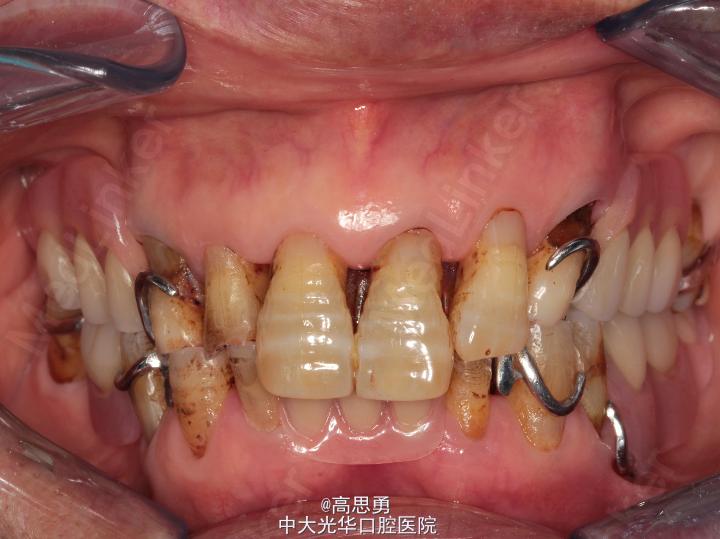

5、口内检查:

#32近中移位约1mm,无明显倾斜

#44远中移位约2mm,向缺隙侧倾斜,伸长约1mm

其余缺牙间隙正常

全口牙龈退缩至根颈1/3,牙龈无肿胀无瘘管

上颌缺牙区牙槽嵴无明显吸收、下颌缺牙区牙槽嵴吸收呈低平刃状

口腔卫生状况欠佳、全口牙石多